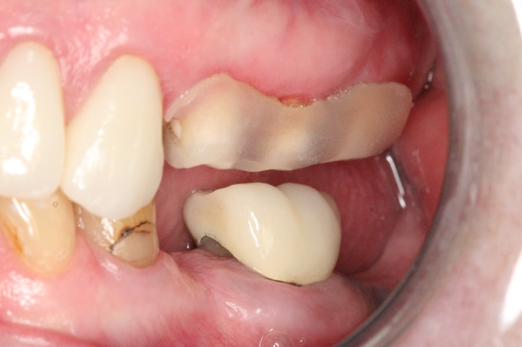

Fig 18. Preoperative image.

Figure 18

Fig 19. Atraumatic extraction.

Figure 19

Occasionally dentists are presented with extreme challenges with long-term restorations and replacing missing teeth. Dentists must evaluate the patient's condition, develop optimum long-term oral health, and attempt to meet the patient's expectations. Figure 18 showed a class III malocclusion with deep bite, multiple abfractions, and less-than-ideal occlusal plane, but the patient wanted to replace his maxillary right canine only. A discussion with the patient regarding occlusal disharmonies and comprehensive recommendations for full-mouth rehabilitation revealed that the patient had a limited budget for dental care. The patient understood the ramifications of his comprehensive dental needs not being affordable. Decisions were made to atraumatically remove the maxillary right canine (Figure 19) and immediately place a ceramic dental implant (Figure 20). Polytetrafluoroethylene (PTFE) 4-0 sutures were placed to help support soft tissues, and then a full-arch Essix-style retainer with a flowable composite facial veneer was used to provide some esthetics during the patient's healing phase (Figure 21). The implant and the retainer were not to be in contactthe retainer may occlude with the opposing dentition and also be passive in relation to the ceramic implant.